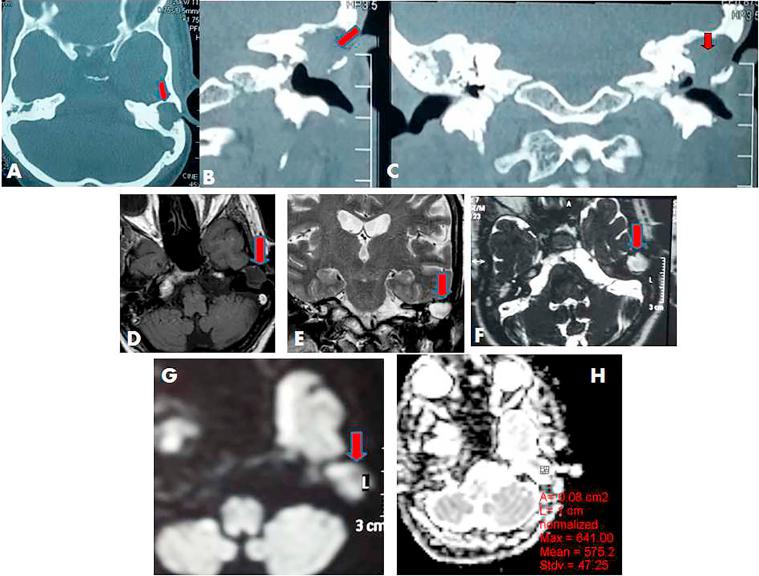

CT showed partial opacification of the tympanomastoid cavity in 10 ears and complete opacification in 21 ears. CT detects 10 cases out of 20 cases of recurrent cholesteatoma with sensitivity 47.6%, specificity 100%, and NPP 47.6%. DWI depicted 21 out of 20 cases proved cholesteatoma patients (sensitivity 100%, specificity 90%, PPV 95.2% and P value is 0.001). All MRI of patients without cholesteatoma were correctly interpreted as showing negative findings for cholesteatoma (specificity = 100%). The ADC of cholesteatoma group (21 ears) were ranged from 553 to 759 × 10 mm/s and the ADCs of non cholesteatoma group (10 ears) was ranged from 1495.8 to 1766.8 × 10 mm/s. Cut off value of cholesteatoma is ≤759 × 10 mm/s.

CT显示鼓室乳突腔部分混浊10耳,完全混浊21耳。CT在20例复发性胆脂瘤中检测出10例,敏感性为47.6%,特异性为100%,阴性预测值为47.6%。DWI在20例经证实的胆脂瘤患者中显示出21例(敏感性100%,特异性90%,阳性预测值95.2%,P值为0.001)。所有无胆脂瘤患者的MRI均被正确解读为胆脂瘤阴性结果(特异性 = 100%)。胆脂瘤组(21耳)的ADC值范围为553至759×10⁻⁶mm²/s,非胆脂瘤组(10耳)的ADC值范围为1495.8至1766.8×10⁻⁶mm²/s。胆脂瘤的截断值为≤759×10⁻⁶mm²/s。